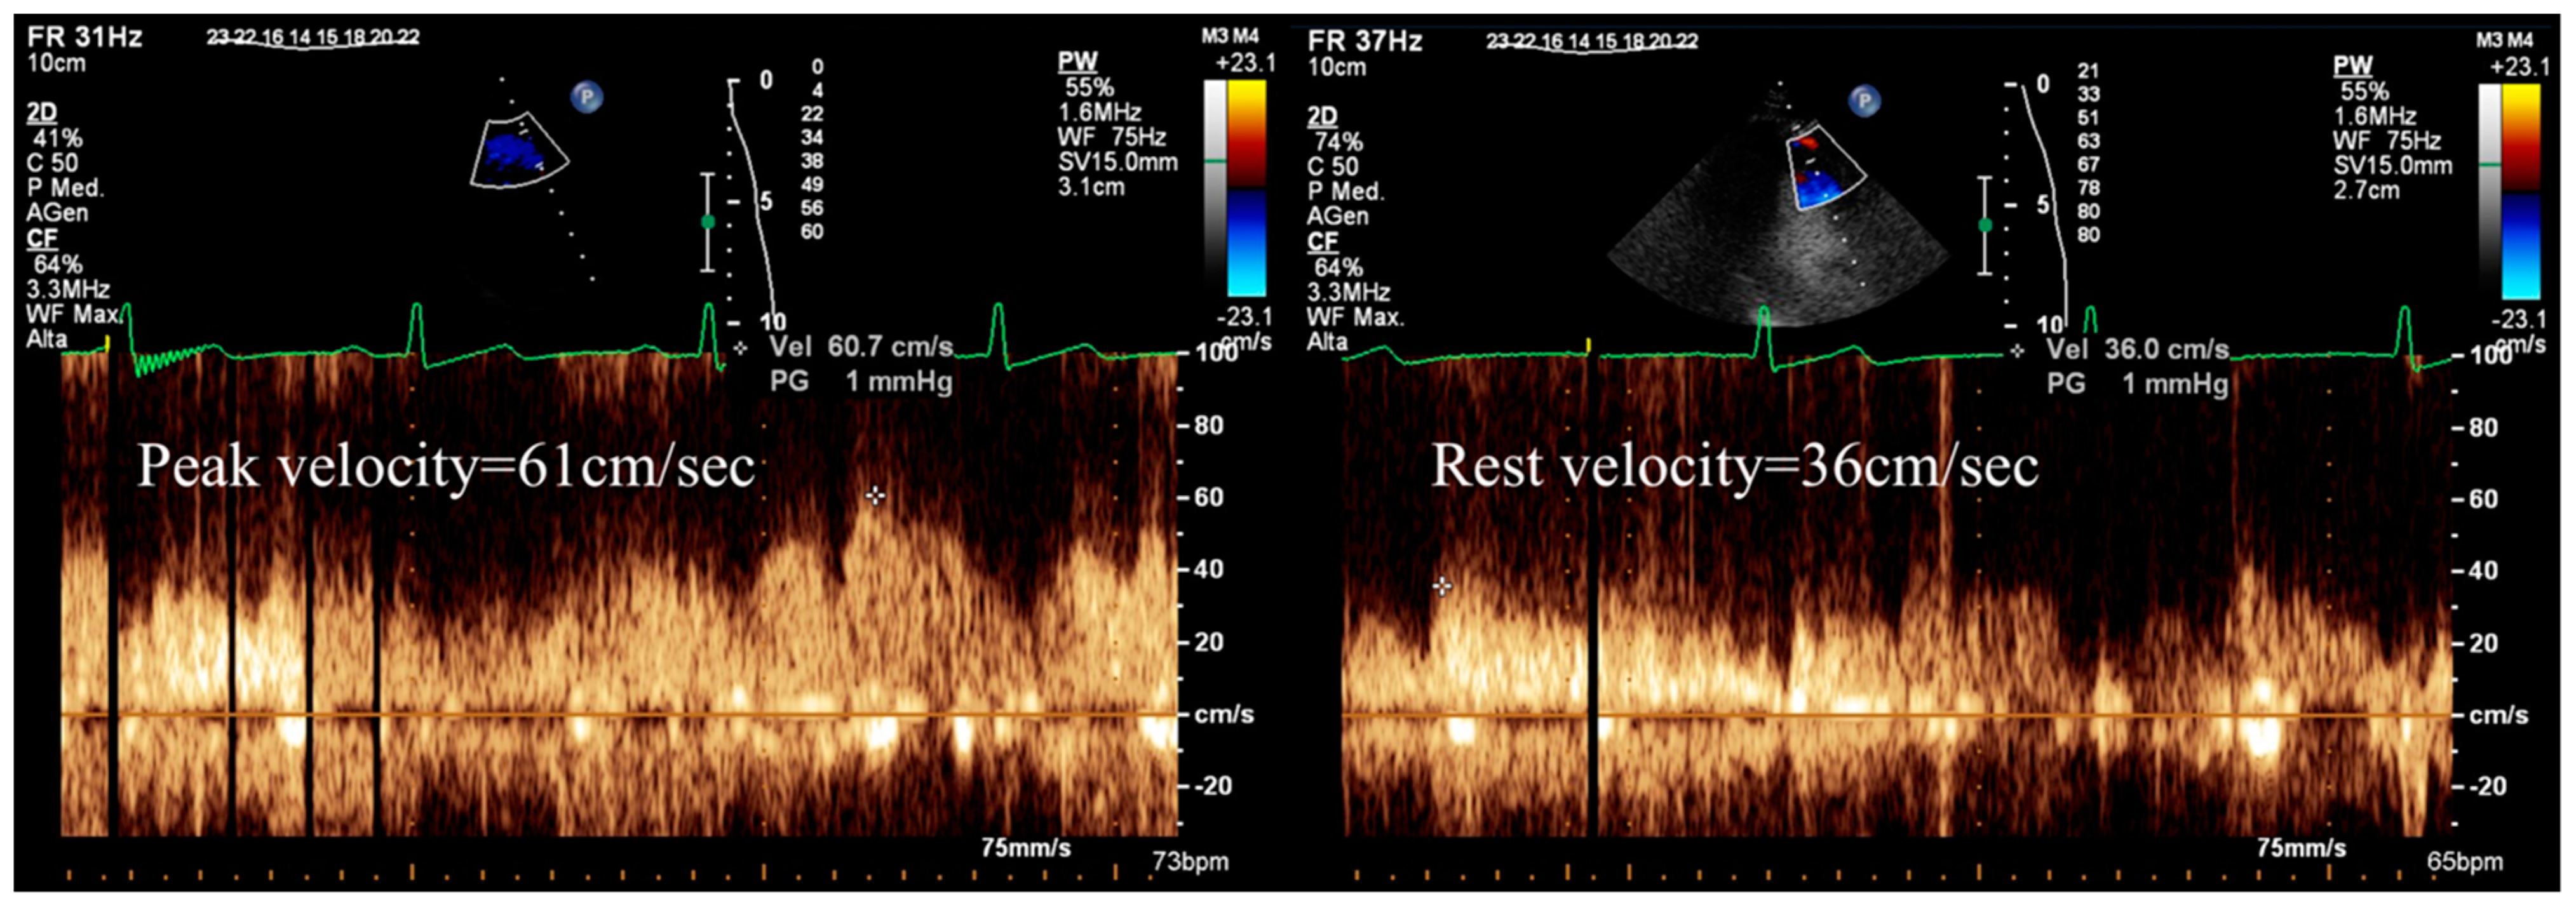

- Gaibazzi, N.; Davies, J.; Tuttolomondo, D.; Pontone, G.; Guaricci, A.I.; Lorenzoni, V.; Benatti, G.; Siniscalchi, C.; Pastorini, G. Association of coronary artery Doppler-echocardiography diastolic-systolic velocity ratio at rest with obstructive coronary artery stenosis on the left main or left anterior descending coronary artery. Int. J. Cardiol. 2019, 281, 1–7. [Google Scholar] [CrossRef] [PubMed]

- Gaibazzi, N.; Picano, E.; Suma, S.; Garibaldi, S.; Porter, T.R.; Botti, A.; Tuttolomondo, D.; Tedeschi, A.; Lorenzoni, V. Coronary Flow Velocity Reserve Reduction Is Associated with Cardiovascular, Cancer, and Noncancer, Noncardiovascular Mortality. J. Am. Soc. Echocardiogr. 2020, 33, 594–603. [Google Scholar] [CrossRef]